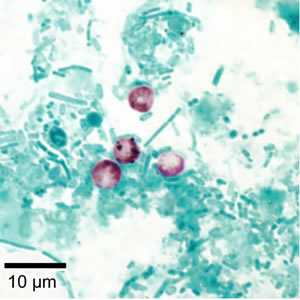

Cryptosporidium parvum